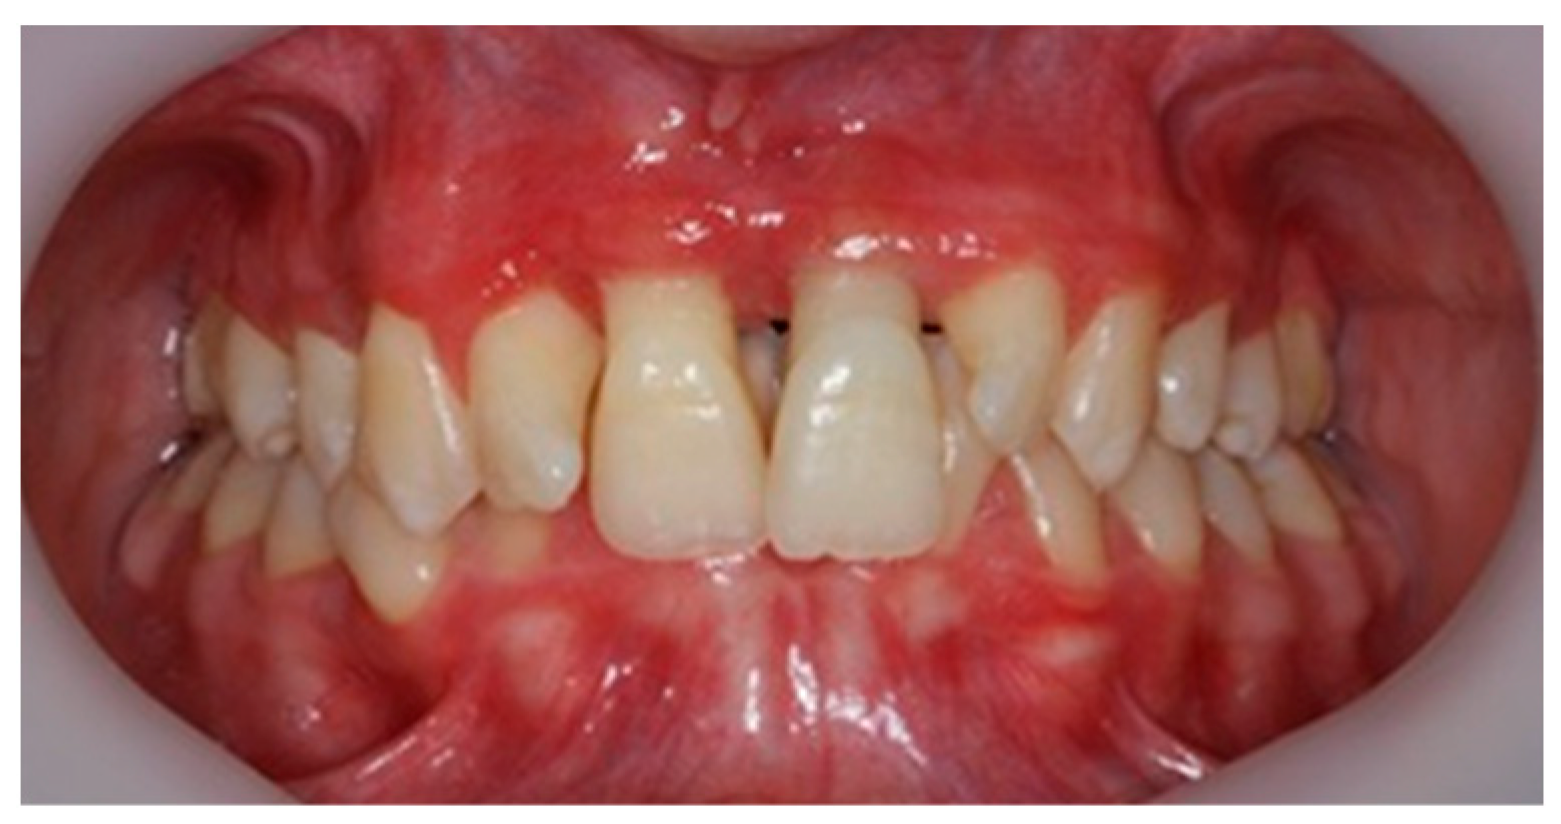

Figure 6.

Clinical aspect after 3 months of periodontal therapy.

After 3 months of phase 1 of periodontal treatment, the patient returned to the clinic for supportive periodontal therapy (Figure 5). The clinically measured gingiva recession was about 6 mm for the maxillary central incisors and 4 mm for the lateral incisors. According to the Miller classification—class III gingival recession—vestibular marginal tissue recession extends to the mucogingival junction. Loss of interdental bone is apical to the CEJ but coronal to the apical extent of the vestibular marginal tissue recession (Figure 5).

The mobility of the teeth (Miller classification) was maintained at Class 2 for the two maxillary central incisors. This mobility was a result of inflammatory edema but also of the high degree of alveolar bone loss (Figure 6). The patient had no discomfort or pain.